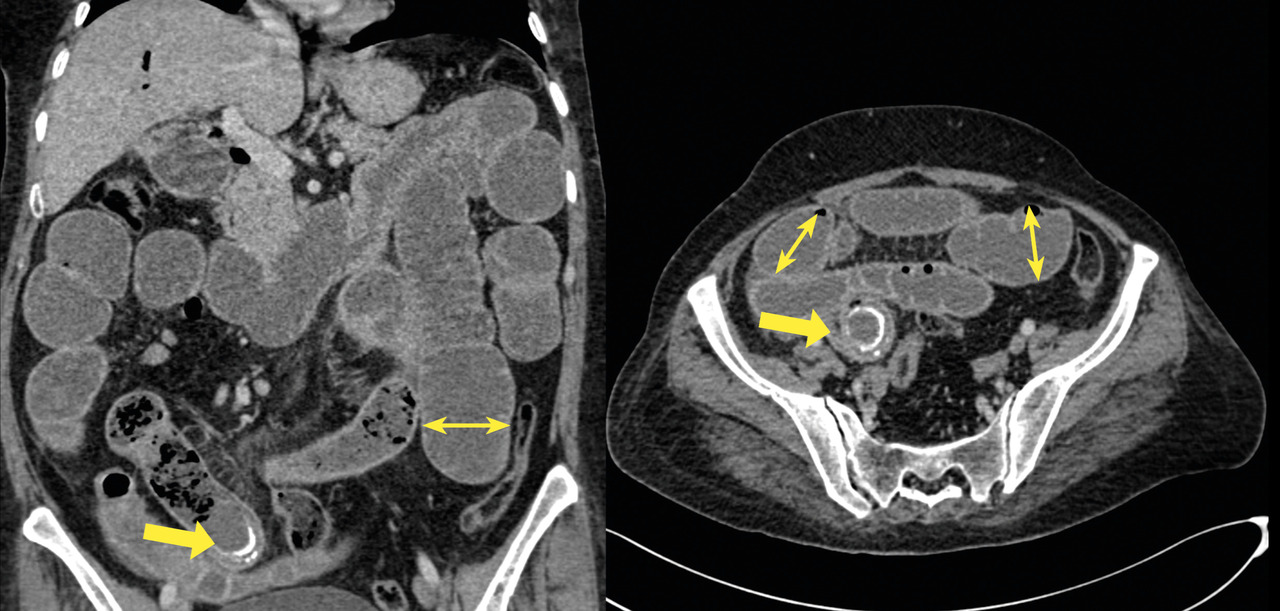

- des bulles d’air au niveau des voies biliaires intra- et extra-hépatique (fig. 3) ;